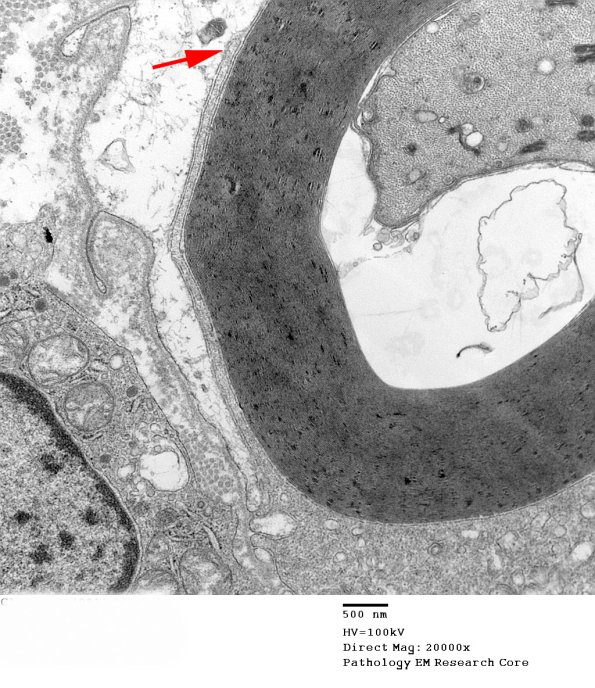

There is minimal myelin phagocytosis with macrophage processes recognizable by their different densities compared to Schwann cell cytoplasm. (electron micrographs)